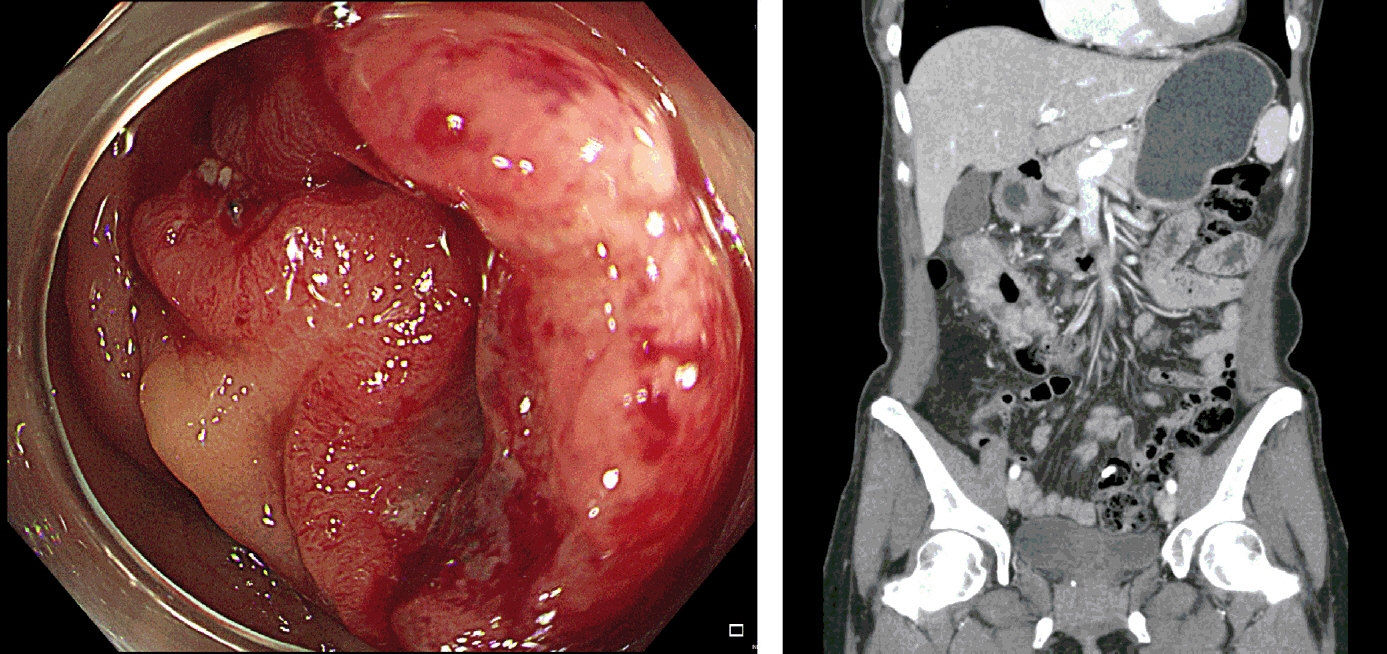

A 44-year-old female was diagnosed with advanced proximal transverse colon cancer during screening colonoscopy. Computed tomography scans revealed a clinical T3 to T4a with node-positive tumor without signs of distal metastasis (Fig. 1). The institutional review board approval was waived.

Figure 1.Initial colonoscopy and abdominal computed tomography images.